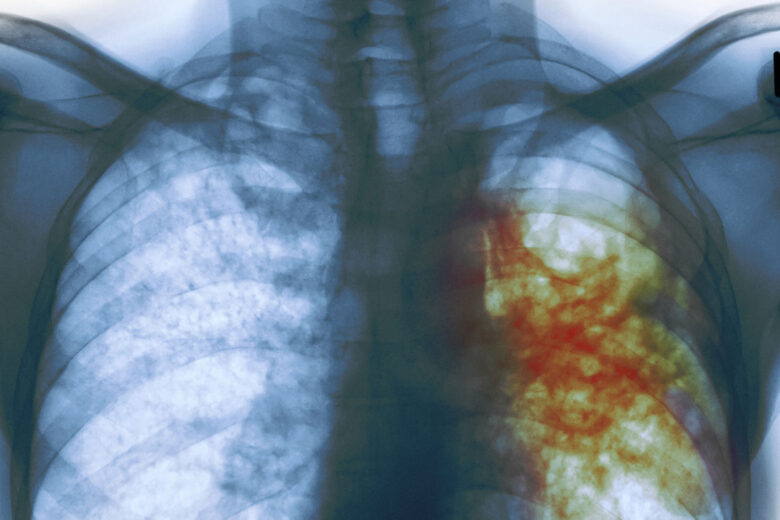

Уровень заболеваемости туберкулёзом в Вологодской области в 2,5 раза ниже общероссийского. Такого результата удалось добиться благодаря системной работе: регулярной флюорографии, обновлению диагностического оборудования и использованию передвижных комплексов, которые позволяют обследовать жителей отдалённых сёл.